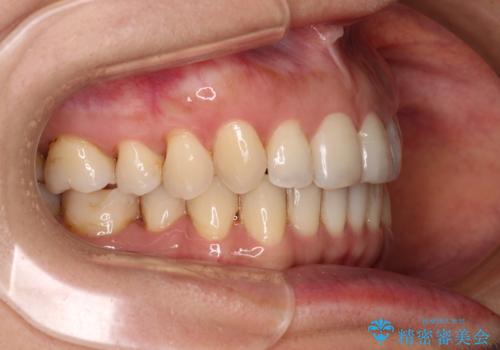

矯正治療の後戻り インビザライン・ライトによる矯正治療

- 患者様

- 40代女性

- 矯正装置

- インビザライン・ライト

- 治療期間

- 11ヶ月

- 矯正治療の後戻りを気にして来院された患者様です。

後戻りは軽微であったので、インビザライン・ライトにより矯正治療を行うこととしました。